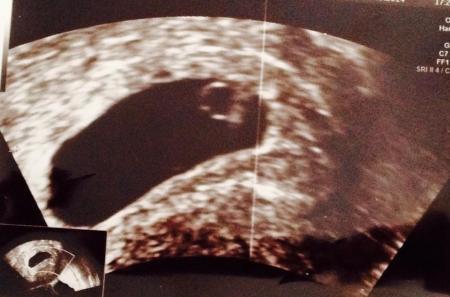

Das Foto ist von mir bei 10+3

Bild zu

Hier sieht man schon deutlich die Finger neben dem Kopf